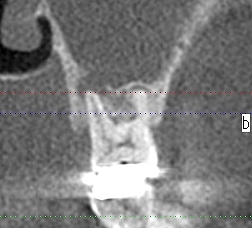

確かに片側だけ上顎洞の肥厚が認められます

7番が明らかに根尖病巣が存在しており、上顎洞に炎症が波及していました

この歯が原因だと理解できました